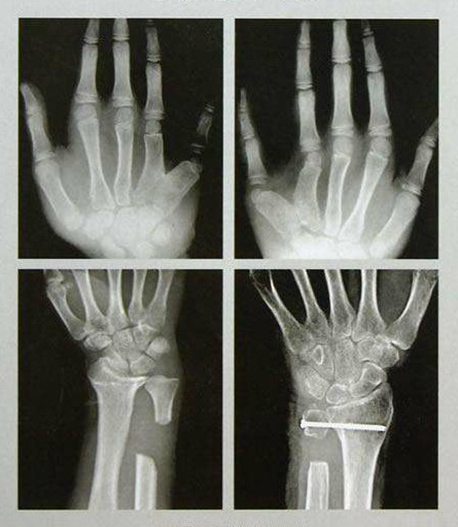

手足外科設(shè)有床位40張,舟山市醫(yī)學(xué)會手足外科專業(yè)委員會主任委員姜德欣主任醫(yī)師擔(dān)任學(xué)科帶頭人。科室提供上下肢和手足部的各種骨折、外傷、感染、畸形、功能障礙的手術(shù)治療,復(fù)雜創(chuàng)傷性四肢的保肢、斷指(趾)再植手術(shù),及各種軟組織缺損的修復(fù)、周圍神經(jīng)損傷、血管損傷的治療及糖尿病足等的綜合治療。